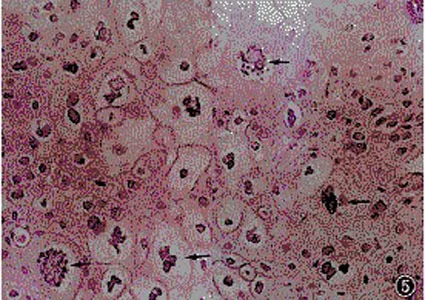

一、组织病理改变 表皮呈乳头瘤样增生,棘层肥厚。表面有轻度角化亢进及角化不全。在棘细胞及颗粒层内可见空泡化细胞,细胞胞体较大,有一圆形深如到育尔染的核,核周空泡化,淡染,在核膜及浆膜间有丝状物相连,使细胞呈猫眼状。空泡化细胞是尖锐基盐粮委空杆吧指却空湿疣的特征性所见,在棘细胞中、上层更为明显。真皮浅层血管周围中等密度浸润,以淋巴细胞为主,还可见浆细胞浸润。真皮乳头部血管扩张,乳头增宽,上延。